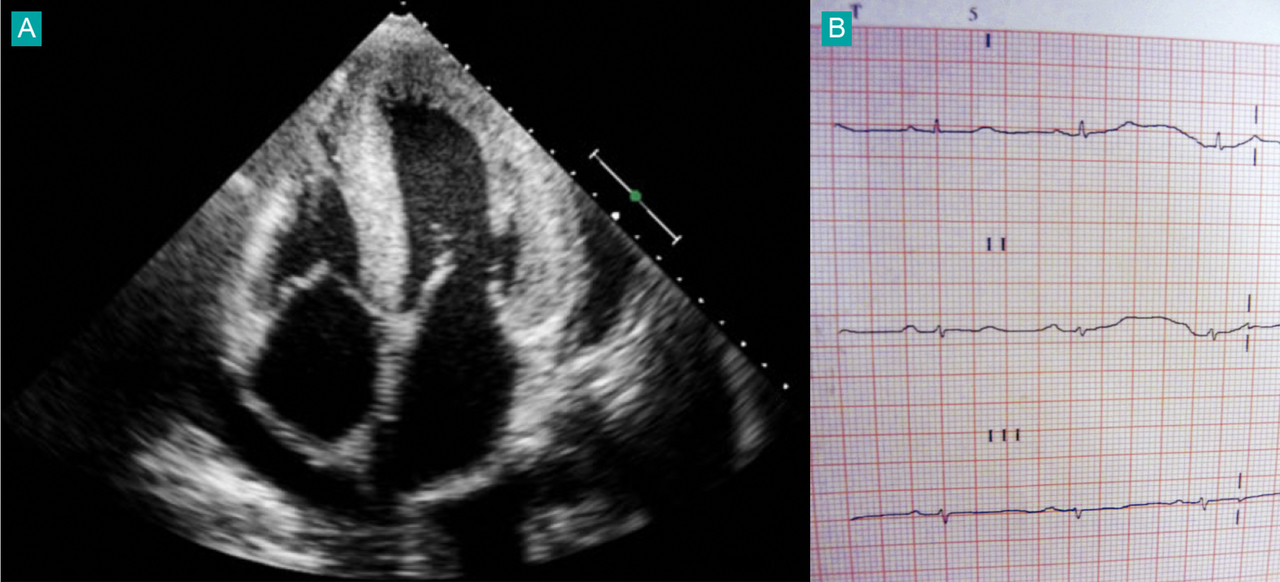

Quel est votre diagnostic ?

Il s'agit d'une amylose cardiaque, échographie (A) et ECG (B). Association cardiopathie hypertrophique et microvoltage très évocatrice du diagnostic. En France, le nombre de nouveaux cas d'amylose AL est de l'ordre de 500 par an. Environ 60 % des patients ont une atteinte cardiaque au moment du diagnostic. Elle constitue le facteur pronostique majeur. Il s'agit d'une cardiomyopathie hypertrophique restrictive, se manifestant initialement par une asthénie et une dyspnée croissante.